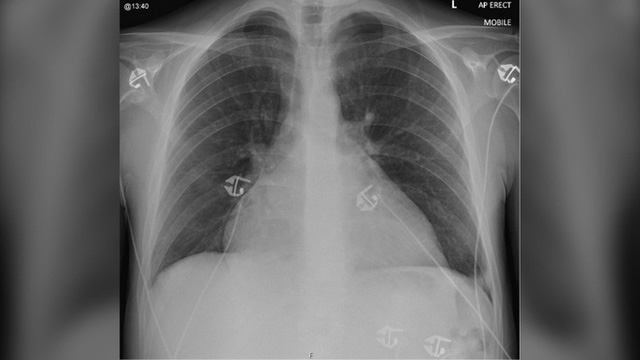

Ghi chép từ nghiên cứu cho thấy ê-kíp chuyên gia phát hiện bệnh nhân bị suy tim, gây cản trở cho khả năng bơm, nhận máu. Trong đầu gối, ổ bụng của người này cũng bị tích đầy chất lỏng. Kết quả chụp X-quang cho thấy tim, phổi, gan của bệnh nhân giãn to. Bệnh nhân buộc phải nhập viện ngay và nằm trong phòng chăm sóc đặc biệt liên tục 58 ngày.

Hình chụp X-quang ngực khi nhập viện của bệnh nhân cho thấy tim có kích thước lớn bất thường. (Ảnh: BMJ Case Reports)